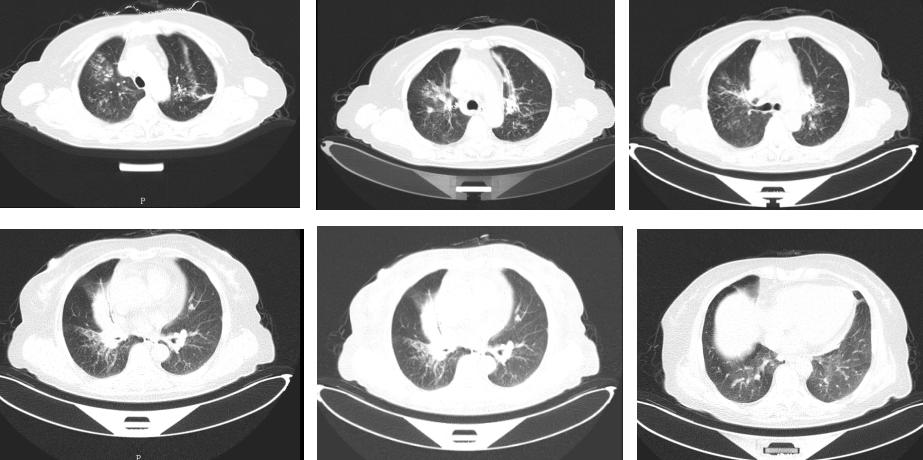

回顾诊疗经过可见,患者症状趋于明显,且影像学提示病变进展。要回答诊断问题还需要继续寻找更多的证据。于是我们复查了气管镜检查(图5):气管通畅,左右主支气管黏膜充血、水肿,表明黏膜粗糙、多发结节凸起,支气管管腔肥厚狭窄,以左肺上叶及右中间支气管为著。再次活检,组织病理提示:组织病理(左上叶、右中间支气管粘膜,图6):肉芽肿性炎,不除外结核,特染:抗酸染色、PAS、六胺银染色均阴性,刚果红染色阴性。肺泡灌洗液未发现抗酸杆菌,TB-DNA阴性,T-SPOT阴性。

图5:第二次住院支气管镜检查

其实,在看到新复查的CT后,我们对患者诊断又有了新的认识,如果说3年前诊断可能排序的时候,首先考虑结核,那么现在基于新的影像学证据我们首先考虑诊断是结节病。为什么呢?胸部CT除发现右肺中叶的肺不张外,同时发现双上肺为著的多发微结节,这些微结节以肺门为中心,沿支气管血管束分布,而非均匀分布,中轴血管束增粗,影像学也更支持结节病诊断。

虽然病理、病原学证据和之前几乎一模一样,然而肺泡灌洗液2次抗酸杆菌阴性、组织病理2次抗酸染色阴性,T-SPOT两次阴性,反复多次找不到结核确诊的直接证据时,间接支持结节病的诊断。同时,ACE升高。患者修订诊断:肺结节病 (II期)。并完善肺功能检查:肺功能检查结果提示轻度阻塞通气功能障碍,弥散功能正常。